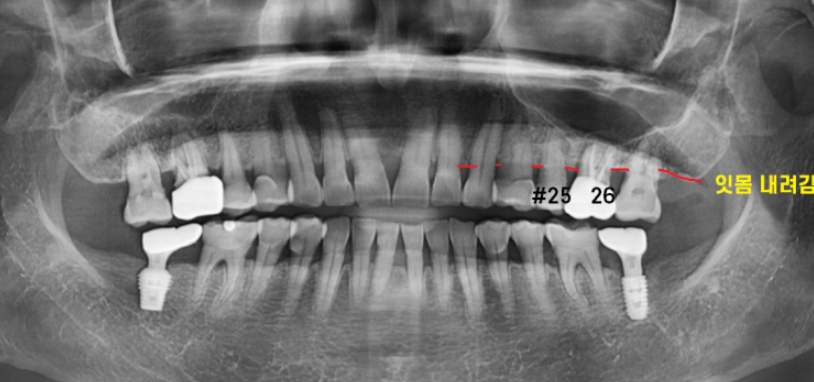

x-ray 먼저 촬영해 보니

잇몸이 전반적으로 내려간 풍치가 발견되었습니다.